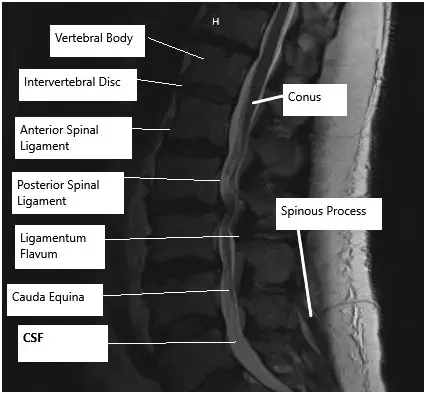

La columna lumbar está formada por cinco vértebras que sostienen la parte inferior de la espalda y permiten el movimiento y la flexibilidad. Entre estas vértebras hay discos intervertebrales que actúan como amortiguadores, absorbiendo los golpes. Las raíces nerviosas se extienden desde la médula espinal a través de aberturas entre las vértebras. Cuando los discos se abultan, hernian o degradan, pueden presionar estos nervios, provocando dolor, entumecimiento y debilidad.

Para diagnosticar problemas de columna lumbar, los médicos utilizan exploraciones físicas para evaluar la movilidad, los reflejos y la fuerza. Las pruebas de imagen, como radiografías, resonancias magnéticas y tomografías computarizadas, ayudan a determinar el alcance del daño, la localización de la compresión nerviosa y si hay inestabilidad vertebral. Estas imágenes guían el proceso de toma de decisiones sobre el tipo de cirugía necesaria.